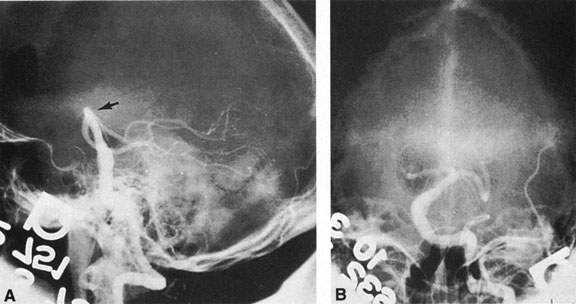

Of particular interest are those AVMs that involve the occipital lobe (Fig. 9). The clinical differentiation of migraine from a cerebral AVM was previously regarded as difficult because the clinical features of occipital lobe AVMs include visual phenomena or headaches. However, in most cases the clinical distinction is possible. In 26 cases with occipital AVM, two distinct syndromes were defined in 18 patients: occipital epilepsy and occipital apoplexy.73 Focal seizures with occipital malformations consist of elementary visual sensations similar to the phenomena evoked by direct cortical stimulations. When seizure activity occurs in the striate cortex (area 17), the patient usually reports sensations of moving lights in the right or left homonymous fields. The sensations are poorly formed, episodic, usually brief, sometimes colored, and unassociated with the angular, scintillating figures so characteristic of migrainous cortical phenomena. Epileptic discharges from areas 18 and 19 cause photopsias that are unlikely to remain stationary and to flicker rapidly. The epileptic photopsias usually last only seconds; occasionally they last for a few minutes before the onset of a generalized seizure. In other instances only the brief visual episodes occur without spreading to produce a generalized seizure. Momentary dimming or blindness in one or both homonymous fields may be experienced with seizure activity in the occipital areas.

Fig. 9. Carotid arteriogram of an occipital lobe arteriovenous malformation (AVM). Lateral (A) and frontal (B) projections demonstrating a small occipital AVM (arrow). The patient was a 23-year-old woman who presented with severe apoplectic unilateral headache, total left homonymous hemianopia, and mild nuchal rigidity. Despite xanthochromic cerebrospinal fluid, she was initially diagnosed elsewhere as having migraine. An AVM was successfully resected, and a small occipital lobe hematoma was removed.

Occipital apoplexy results from hemorrhage and hematoma formation within the occipital lobe and is characterized by sudden severe headache and homonymous visual field loss. Homonymous hemianopia is the most important sign produced by vascular malformations of the occipital lobe. Compression and necrosis of visual pathways by an intracerebral hematoma are the principal mechanisms. Usually the hematoma is large and tends to split or dissect longitudinally through the white matter of the occipital lobe. The effects of compression may be reversed by prompt, surgical evacuation of the hematoma.73 With hemorrhage into one occipital lobe, hemianopia in the visual field of the contralateral normal occipital lobe may develop, producing total blindness that can last for several days. The rapidly expanding hematoma may shift the damaged hemisphere anteriorly, or across the midline, with downward herniation of the uncus through the tentorial incisura. This shift compresses the posterior cerebral arteries and accounts for bilateral occipital lobe dysfunction. Arrest of function in the undamaged occipital lobe may be due to an interhemispheral inhibitory phenomenon termed diaschisis. Visual field defects with occipital AVMs are regularly due to hemorrhage and hematoma formation. Congenital arteriovenous malformations can occupy the entire occipital pole (the macular projection area) for decades without producing visual field defects.

Although migraine is often cited as a symptom of AVM, it is extremely rare that classic migraine is mimicked by occipital AVM. None of the patients in the series by Troost et al73 described the 15- to 20-minute episodes that characterize the visual aura of classic migraine. The headaches of AVM differ from migraine in that they are constantly localized to the same side of the head, and intermittent visual phenomena, if present, can persist throughout the headache or even after, whereas in migraine the visual phenomena usually precede the headache. Bruyn74 has reviewed the clinical features of 57 reported and 7 personal cases of AVM, concluding that the migraine of AVM is late onset, nonfamilial, and brief. Rarely, the complete clinical symptomatology of classic migraine can be mimicked by an occipital lobe AVM (see Chapter 16).75 In addition to hemianopia, other visual disturbances can occur after hemorrhage into the occipital lobe, including alexia without agraphia (see Chapter 7).